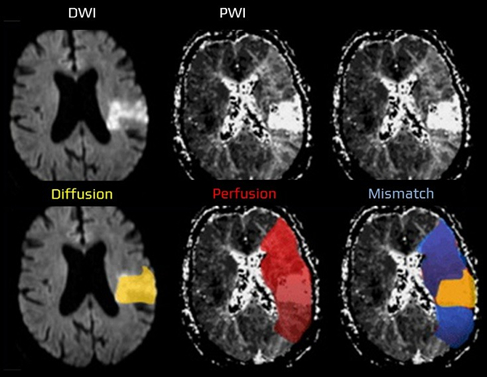

Hypoperfusion in acute ischemic stroke indicates a hemodynamic disturbance visible across multiple MRI contrasts [Forkert et al., 2013]. Each modality provides complementary in- formation: susceptibility-weighted imaging (SWAN/SWI) and phase highlight venous de- oxygenation, time-of-flight (TOF) angiography captures arterial inflow and distal signal loss, diffusion-weighted imaging (DWI) shows early cytotoxic injury, and FLAIR reveals hyperin- tense vessels and edema [Mittal et al., 2009].

This project builds on the observation that, even without perfusion imaging, other MRI se- quences contain physiologically related cues. These can be combined to infer the hypoperfused volume [Oktay et al., 2018]. The main scientific goal is to develop a hetero-modal encoder that integrates any subset of sequences into a unified latent representation, from which a realistic hy- poperfusion map can be reconstructed while preserving anatomical, physical, and inter-sequence consistency.

Quantify the ischemic ”mismatch” (penumbra) as the vol- ume difference/ratio between perfusion deficit and diffusion core, and assess its clinical utility for reperfusion triage when onset is uncertain and for prognosticating treatment benefit. Deliverables include code, trained models, ablation studies, and validation on retrospective cohorts with report- ing suited for a manuscript draft.